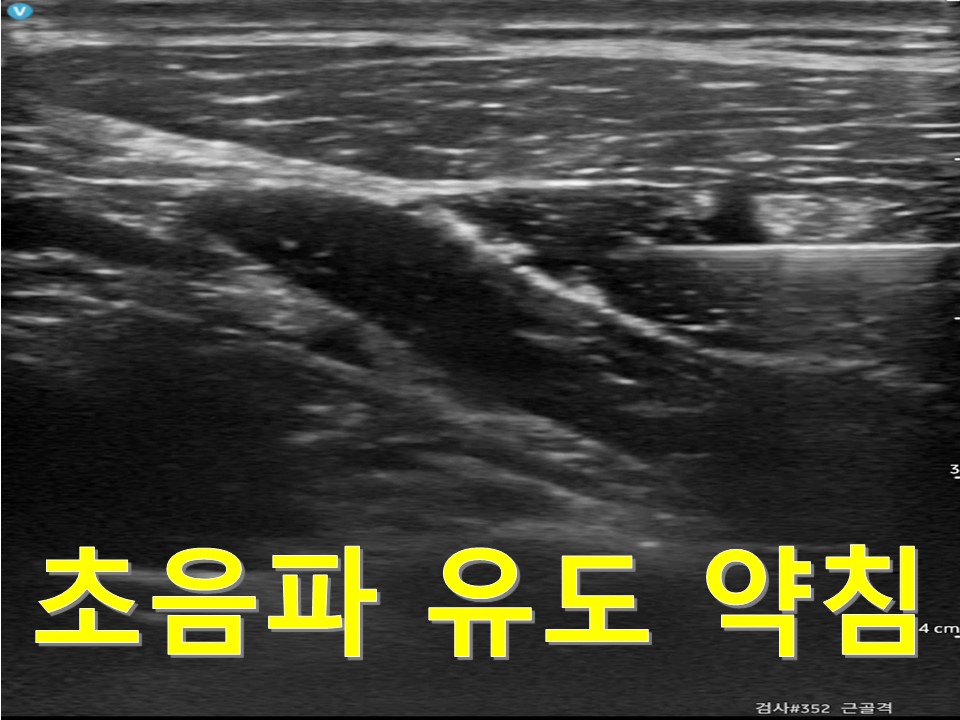

환자의 증상에 따라 침구치료와 부항치료 뿐만 아니라,

원장이 직접 추나, 약침, 한약 처방 및 조제를 시행하고 있습니다.